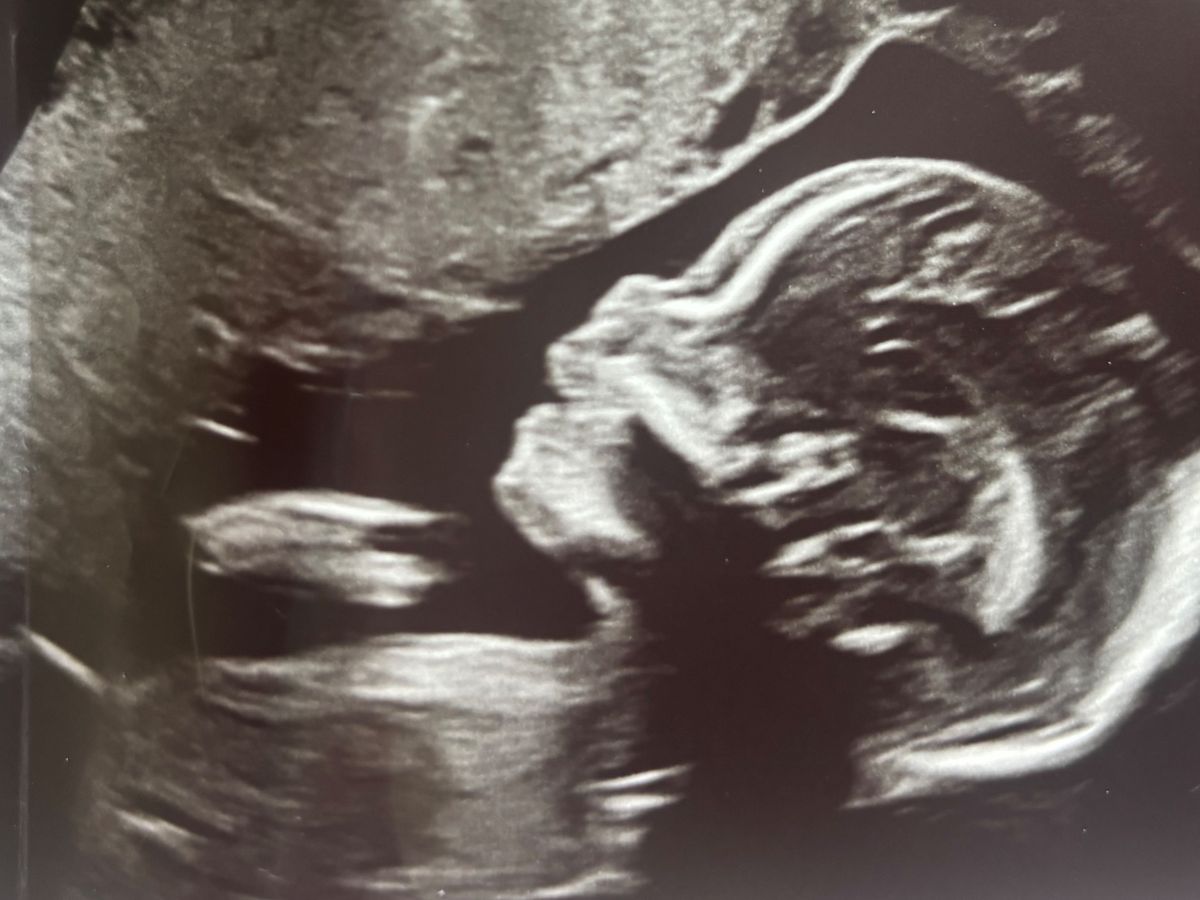

We received heartbreaking news that our baby’s heart is underdeveloped on the left side—a condition known as Hypoplastic Left Heart Syndrome. This means he won’t be able to survive outside of the womb without immediate surgery after birth, and he will need at least two more surgeries as a baby. Even after these procedures, he will face lifelong heart complications, and many children with this diagnosis require additional surgeries throughout their lives.

This diagnosis has turned our world upside down- as we are concerned for our son’s wellbeing. We are preparing for a long out of town hospital stay for the first surgery and we will be out of work for an estimated three months while our baby receives the care he needs. The emotional and financial strain is overwhelming, but we are determined to do everything possible for our sweet baby James.